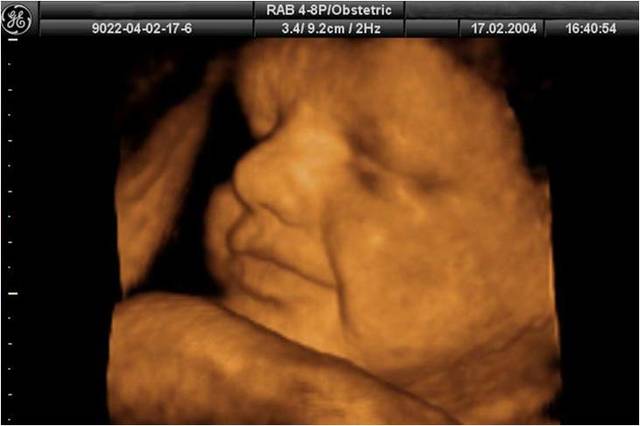

• Semana 11- 14

Semana 11- 14

Los párpados del feto se cierran y no se vuelven a abrir casi hasta el final de la gestación. La cara del feto ya se encuentra formada aunque su cabeza sigue siendo muy grande sin proporción con el resto del cuerpo. Las extremidades son largas y delgadas. En estas semanas se desarrollan las uñas de los dedos. El hígado ya produce glóbulos rojos y sus manos ya pueden formar puños.